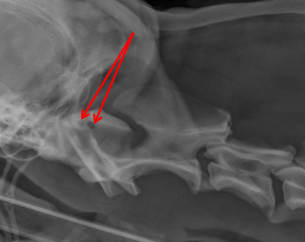

ID Radiographic View

Frontal Sinus View

ID

Frontal Sinus

Ethmoid Turbinates

Maxillary Turbinates

Nasopharynx

Maxillary Recess